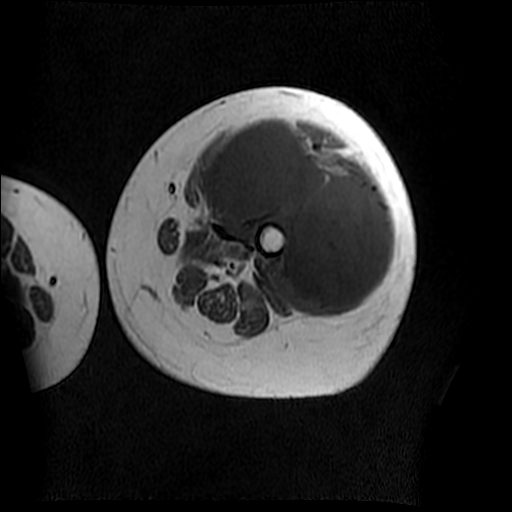

左侧大腿外伤10余年,当时情况不清,发现左侧大腿肿胀7年余,而后又有多次外伤史,近1年来出现疼痛,减重半年。查体:左侧大腿肿胀明显,皮温、肤色正常。

软组织肿块,股骨破坏,增强不均匀强化-----支持恶性肿瘤